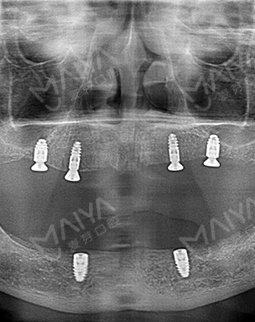

我的牙齿情况比较严重,长期缺牙,不仅缺的数目多,而且骨量出现了萎缩。虽然说麦芽的博士专家团,给我做了all-on-4种植的方案,但还需要结合骨增量来夯实地基。缺牙后提前种牙的好处,就是不会像我一样,出现严重的骨萎缩了。好在麦芽的医生种牙实力很过瘾,我现在四颗钉基本就撑起了半口牙齿,费用真的比单颗单颗种牙,节省了很多!